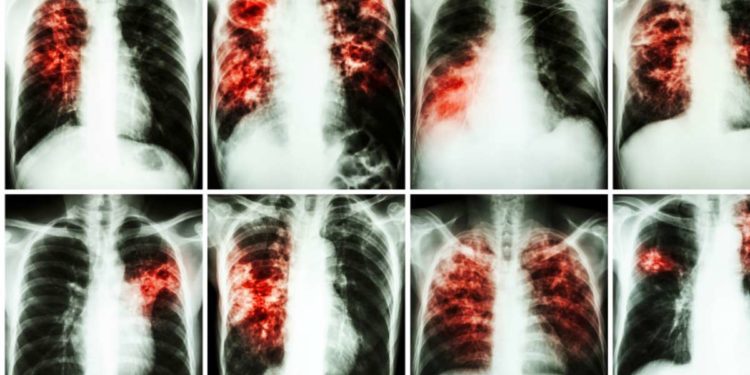

“La fibrosi polmonare idiopatica (IPF) è una malattia rara, cronica e progressiva che colpisce il fragile tessuto polmonare, con un deterioramento graduale e persistente della funzionalità di questo organo. L’IPF – afferma Mario MALERBA, Professore di Malattie dell’Apparato Respiratorio del Dipartimento Medicina Traslazionale (DIMET) dell’Università del Piemonte Orientale (UPO) e Direttore della SCDU di Pneumologia- Ospedale S. Andrea, ASL di Vercelli – si manifesta tipicamente dopo i 45 anni e l’età media dei pazienti colpiti è 65 anni ed ex fumatori”.

“I sintomi che si manifestano sono tipicamente tosse secca e dispnea con andamento ingravescente. La diagnosi precoce consente di intervenire farmacologicamente, rallentando il degrado della funzionalità respiratoria, e di trattare le complicanze correlate al suo peggioramento.